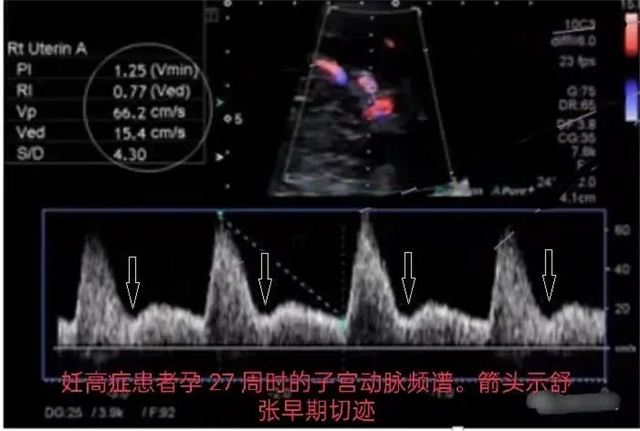

为什么需要进行子宫动脉的超声检查呢? 这个测量数值正常吗? 这个测量结果影响我怀孕吗? 怀孕后会影响宝宝生长发育吗? 这是许多孕妈妈或者备孕妈妈 经常问的问题, 今天超声科李琴医生和大家聊聊 子宫动脉的超声检查有必要吗? 为何要查子宫动脉? 子宫是孕育生命的摇篮,子宫动脉及其分支为它提供源料,输送营养,为胚胎发育做好准备。怀孕后,子宫动脉将富含营养物质的母血送至胎盘,与胎儿血液进行物质交换。子宫内膜如同种子发育的土壤,子宫动脉及其分支为摇篮和土壤提供源源不断的血供和营养,保证胚胎发育所需要的各种养分。 如何检查动脉血流? 检查时间尽量安排在排卵后的3-5天,也可以适当放宽到排卵后7天。这个时候最能反应胚胎着床时期的内膜血流情况,得到的数据往往最具参考意义。 目前也有观点认为检测时数据容易受到自身状态的影响,一次异常不具有参考性,尽量多次检测。 子宫动脉监测的意义 在孕前子宫动脉血流指数在月经周期的不同时段会有所不同,正常情况下,排卵后的黄体期也就是受精卵着床时期间子宫动脉的血流量增加,这对受精卵着床就非常有益。PI和RI值越低说明卵巢和子宫的血流灌注情况越好,胚胎着床率也就越高。如果子宫动脉血流异常,可能会导致胚胎发育不良,复发性流产,反复种植失败等。 子宫动脉血流并不仅仅在备孕前很重要,而且在怀孕时也非常的重要,因为它就是给子宫供血的。妊娠后,子宫动脉将富含营养物质的母血送到胎盘,跟胚胎的血液进行物质交换。如果子宫动脉异常会引起相应得很多疾病,如妊高症、胎儿宫内生长受限或羊水过少时,子宫动脉阻力不再呈现由高逐渐变低的下降趋势,甚至会有升高。 结果怎么看? 通过检查测量子宫动脉血流动力学的各种参数来了解子宫动脉供血情况,这些参数包括:血流阻力指数(RI)、搏动指数(PI)及收缩期峰值/舒张末期流速(S/D)这3个数值。 子宫动脉血流参数参考值: 在月经周期的不同时段,血流参数会有不同。比如在排卵后的黄体期(受精卵着床时期),子宫动脉血流量增加,对受精卵着床非常有益。此时子宫动脉由高阻低血流逐渐转变为低阻高血流状态,RI、PI和S/D值逐渐降低,舒张早期切迹变低至消失。此时的参数值一般以RI<0.85、PI<3、双侧S/D之和<12为准。 一旦确定怀孕,在孕早期内膜血流阻力会逐渐下降,舒张期早期切迹逐渐消失;此时的参考标准为:RI<0.85、PI<2.3、S/D两侧之和<12。 *目前临床上没有统一指南,以上参考数据仅供参考。 孕期正常子宫动脉血流参数参考值: 时期 早孕期 中孕期 晚孕期 RI <0.75 <0.73 <0.58 PI <2.25 <1.5 <0.82 S/D <6 <3.6 <2.6 不同病变的参数特征 *子宫动脉舒张早期切迹在孕 20 周后,随胎盘阻力降低而逐渐消失。若孕 26 周后,舒张早期切迹持续存在(箭头所示),可提示胎盘循环阻力增高,同时结合频谱 RI 异常能有效提高妊高症的检出率。 *患者若存在不孕症、胚胎发育不良、复发性流产、反复种植失败等病史时,可表现有子宫动脉血流阻力增高(表)。 表 不同病变黄体期子宫动脉血流参数 时期 不孕症 流产 RI >0.89 >0.85 PI >3.5 >2.5 S/D >8 >8 专家推荐 陈亚东 主治医师 超声科副主任 影像医学与核医学硕士研究生 专研肌肉、骨骼、关节以及关节辅助结构和邻近软组织,包括韧带、肌腱、滑囊、滑膜、神经、软骨等的肌骨超声诊断及超声引导下的穿刺活检、病理性囊液置管引流等的超声介入诊疗工作。曾获得中华医学会全国超声医学学术优秀论文;长治市科技进步奖应用类二等奖等。 李琴 副主任医师 擅长腹部、妇产科、血管及浅表等超声诊断,有着较丰富的经验。从事超声医学诊断工作已二十余年,曾在山西医科大学研修班学习,山西省人民医院进修,发表省级以上论文多篇。 供 稿丨李 琴 编 辑丨翟艳鹏 审 核丨雷 赫